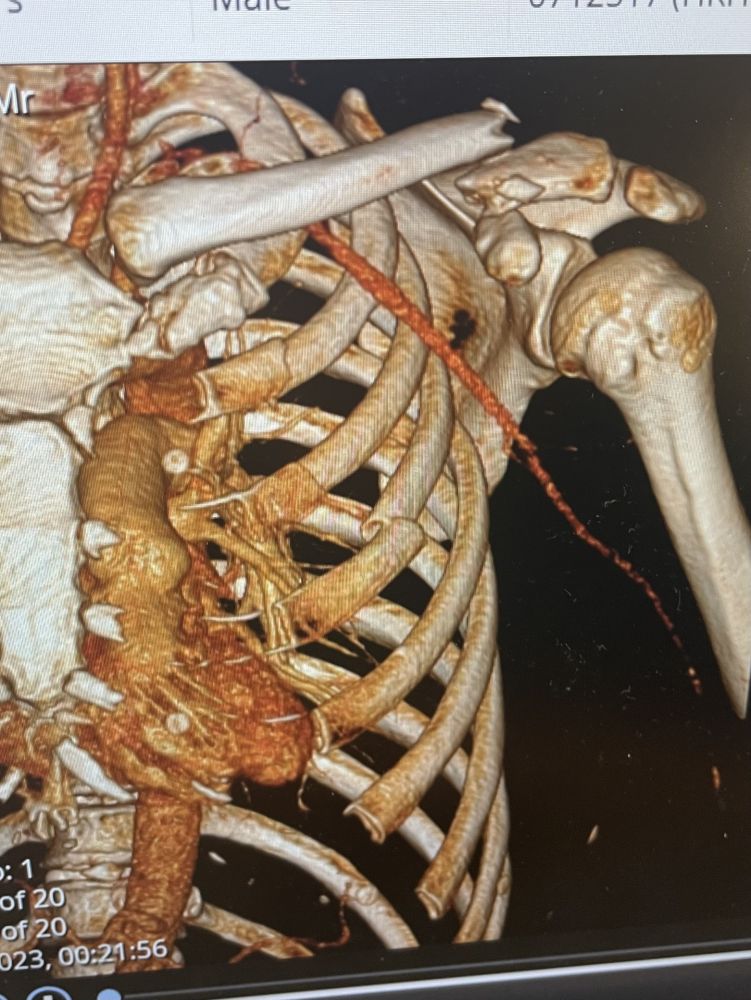

这一跤摔的不轻啊,锁骨完全断开。

医疗报告说肋骨2,3,4 fractured。我看1也应该是fractured吧?哪位会看的有经验的指点一下